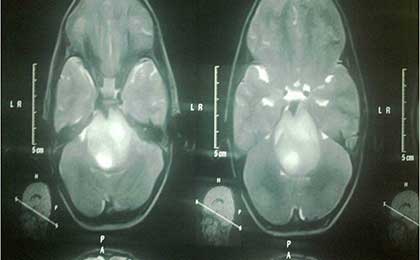

Brain Stem Glioma 2

• Brain Stem Glioma 2